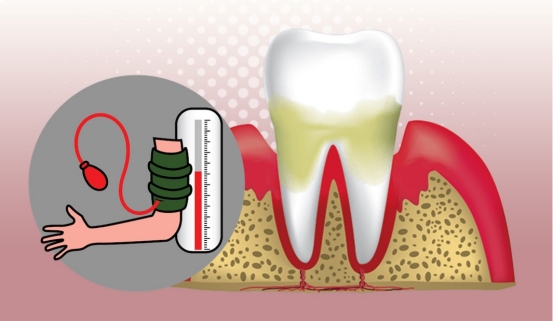

对于高血压的患者,血压控制在180/100mmHg以下,一般可以耐受拔牙。高龄的高血压患者,术前血压最好控制在160/90mmHg以下。

高血压与拔牙